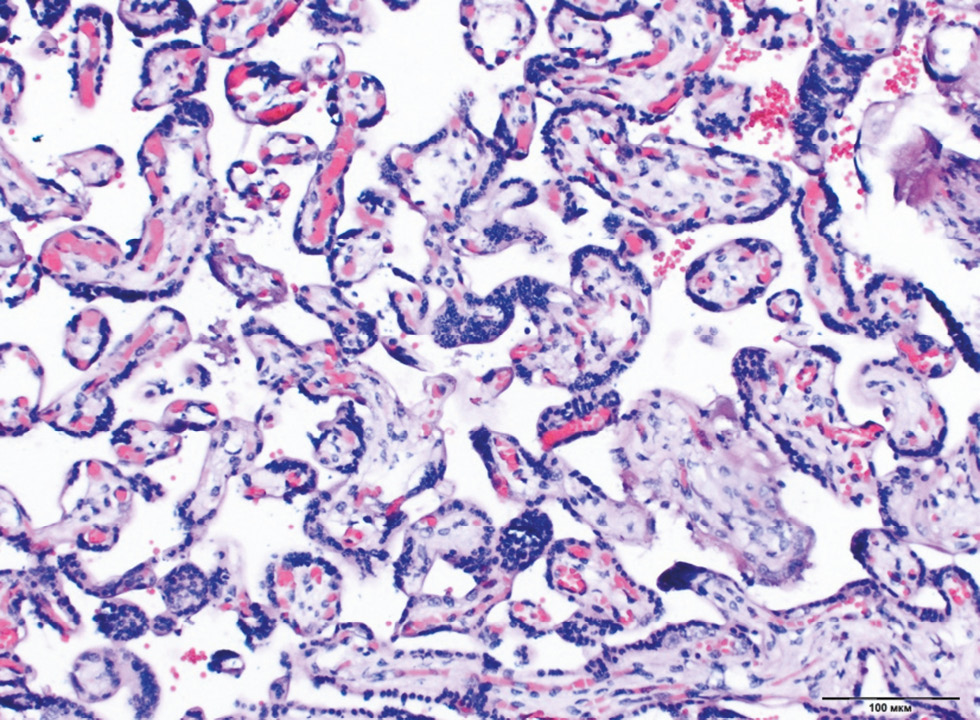

Chronic placental insufficiency was typical for all groups of DM and PE, in contrast to the control group (p < 0.0001). Placental insufficiency was registered in 39.6% of cases in Group 4 (type 2 DM on a diet), 37.2% in the type 1 DM group with MII, whereas pathological immaturity of villi was noted more often in the same groups (14.2% and 19.5%, respectively). In general, pathological immaturity of villi was typical for all groups of DM (9.5%–19.5%, p < 0.0001). The predominance of intermediate immature villi was a characteristic of type 1 DM with MII (13.3%, p = 0.036) (Fig. 1). The dissociated form of chronic placental insufficiency was most often detected in DM (16.3%–26.1%) (Fig. 2). The prevalence of sclerosed villi (0.4%–3.3%) and premature maturation of villi (0.4%–5.0%) were revealed less frequently. In the PE group, the premature maturation of villi was noted often (7.7%, p < 0.0001). In the control group, 93% of placentas corresponded to gestational age (Table 2).

Fig. 1. Chronic placental insufficiency with a predominance of intermediate immature chorionic villi with hypervascularization and congestive plethora in type 1 DM. Staining with hematoxylin and eosin, ×100